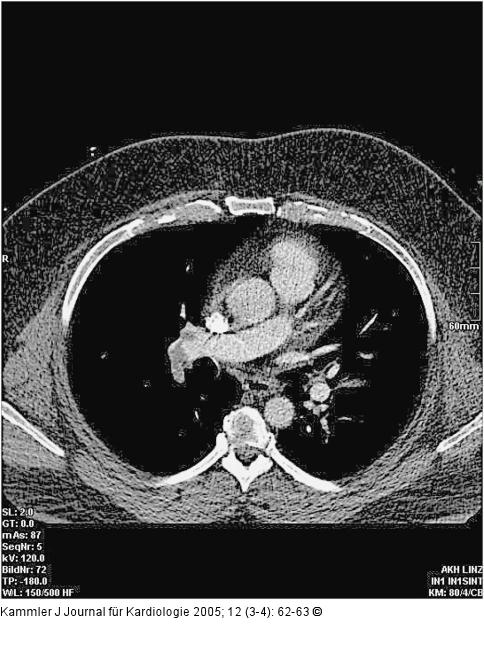

Abbildung 2: Zentrale Pulmonalembolie Zentrale Pulmonalembolie rechts mit einem Sattelembolus der Unterlappenarterie und Kontrastmittelaussparungen aus der A. pulmonalis in die Ober- und Mittellappenarterie; die rechte Pulmonalarterie mit 2,5 cm sowie der Truncus pulmonalis mit 3,4 cm ektatisch. |

Abbildung 2: Zentrale Pulmonalembolie

Zentrale Pulmonalembolie rechts mit einem Sattelembolus der Unterlappenarterie und Kontrastmittelaussparungen aus der A. pulmonalis in die Ober- und Mittellappenarterie; die rechte Pulmonalarterie mit 2,5 cm sowie der Truncus pulmonalis mit 3,4 cm ektatisch. |